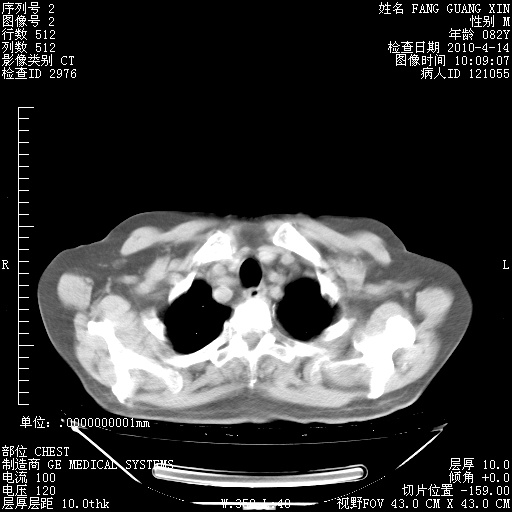

肺部CT平扫未见异常。